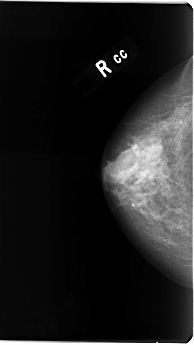

B_3076_1.RIGHT_CC

RIGHT_CC LINES 4824 PIXELS_PER_LINE 2712 BITS_PER_PIXEL 12 RESOLUTION 50 NON_OVERLAY